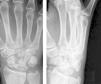

Material y métodoEntre 2007 y 2010, se trataron en nuestro centro 3 pacientes (2 varones y una mujer) con síndrome de Fenton. La edad media fue de 26 años (19, 21 y 32 años) y la muñeca afectada fue la derecha en todos los casos. Dos de los 3 pacientes referían haber sufrido la lesión como consecuencia de un accidente en motocicleta, mientras que en el restante fue debida a una caída casual. En todos los casos se presentó dolor y tumefacción importante del dorso de la muñeca. El estudio radiográfico, mediante proyecciones anteroposterior, lateral y oblícua, mostró la asociación de ambas fracturas junto con la rotación de más de 90° de la cabeza del hueso grande con respecto al resto del hueso (fig. 1).

También el estudio mediante TC, permitió objetivar la rotación del fragmento proximal del hueso grande (fig. 2).